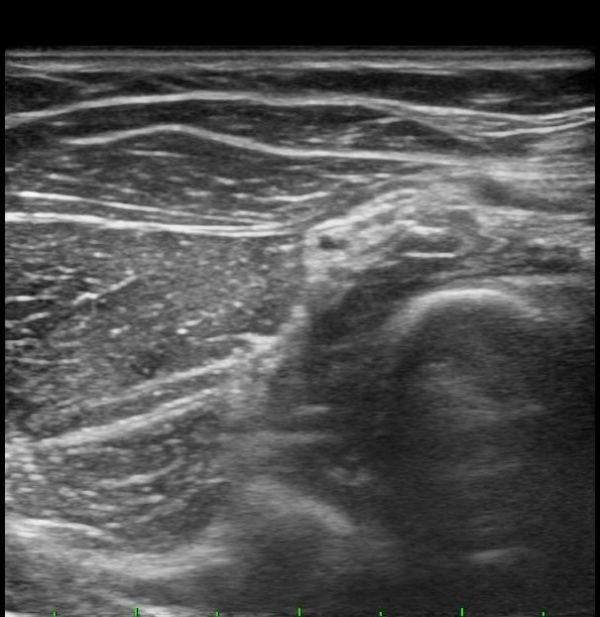

ŽÃËÀÚÀ» ¸»´ÜÀ¸·Î À̵¿ÇÏÀÚ Èİñ°£½Å°æÀÌ È¸¿Ü±Ù ±ÙÀ§ºÎ¿¡¼­ Àú¿¡ÄÚ ºÎÁ¾À» º¸ÀÓ(±×¸² 2).

ŽÃËÀÚ¸¦ Á» ´õ ¸»´ÜÀ¸·Î À̵¿ÇÏ´Ï Èİñ°£½Å°æÀÌ È¸¿Ü±Ù ¸»´Ü¿¡¼­ Ç¥ÃþÀ¸·Î ³ª¿À´Â °ÍÀÌ °üÂûµÊ(±×¸² 3).

¾Æ·§ÆÈÀ» ȸ³» À§Ä¡¿¡¼­ Èİñ°£½Å°æ Á¾´Ü¸é°Ë»ç¸¦ ½ÃÇàÇÏ´Ï Èİñ°£½Å°æÀÌ µÎ ȸ¿Ü±Ù »çÀÌ¿¡¼­ ¾Ð¹Ú¹Þ°í ȸ¿Ü±Ù ±ÙÀ§ºÎ¿¡¼­ Àú¿¡ÄÚ ºÎÁ¾ÀÌ °üÂûµÊ(±×¸² 4, 5).